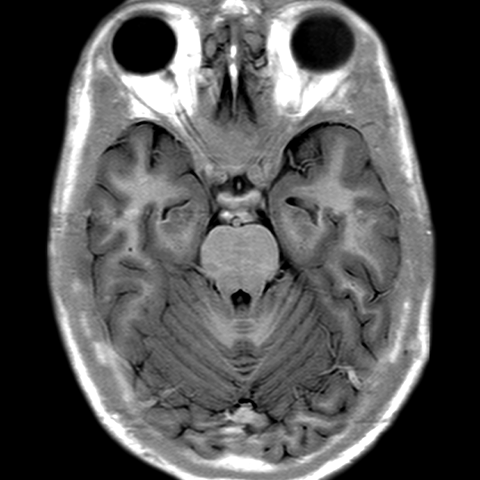

Cerebral Hemispheres, MR (normal) [6 of 9]